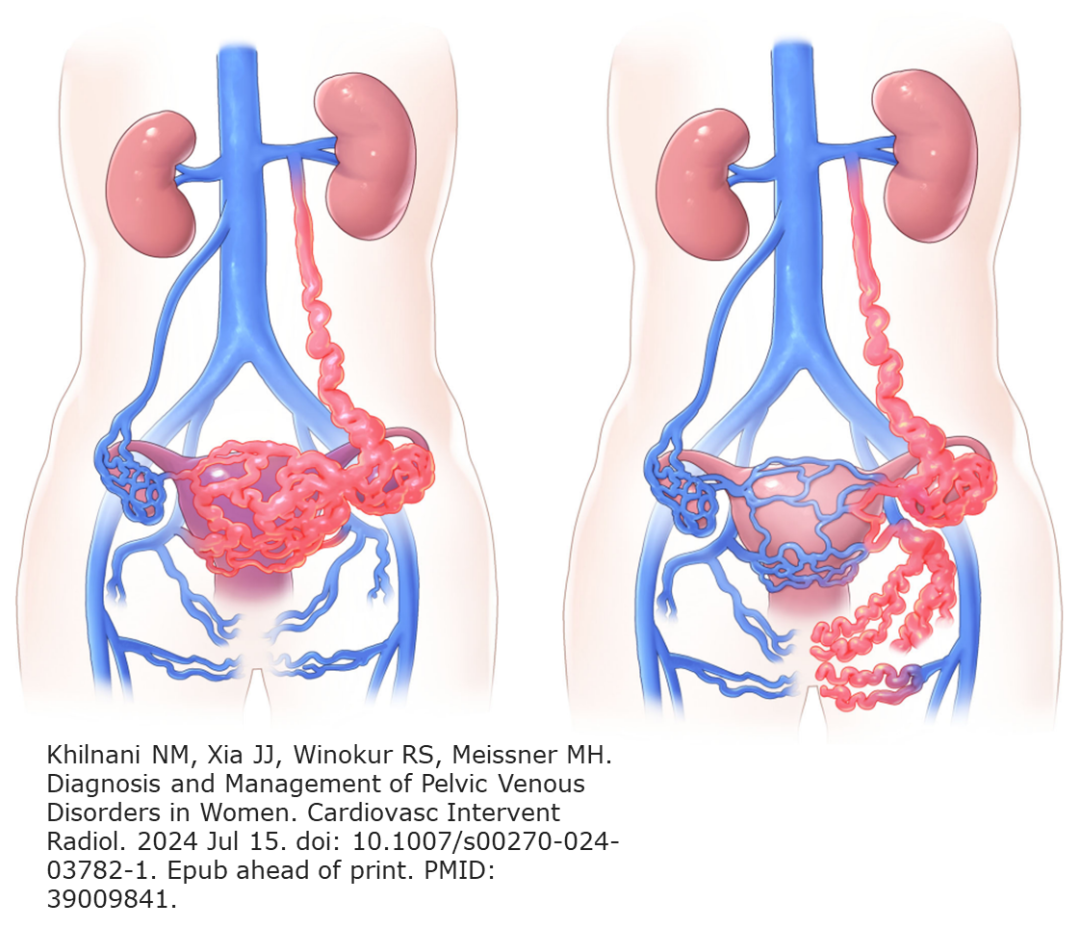

我们团队借鉴 CHIVA 理论,提出形象化的“蓄水池”模型解释疾病进展:

第一蓄水池(盆腔):

卵巢静脉/盆腔静脉反流 → 盆腔静脉高压 → 出现慢性盆腔痛、性交痛等症状。

第二蓄水池(下肢/会阴):

当盆腔压力持续升高,血液通过逃逸点向下代偿分流 → 形成会阴、大腿、臀部甚至下肢静脉曲张,此时盆腔症状可能反而减轻,但下肢问题凸显。

病理生理:非代偿性 代偿性